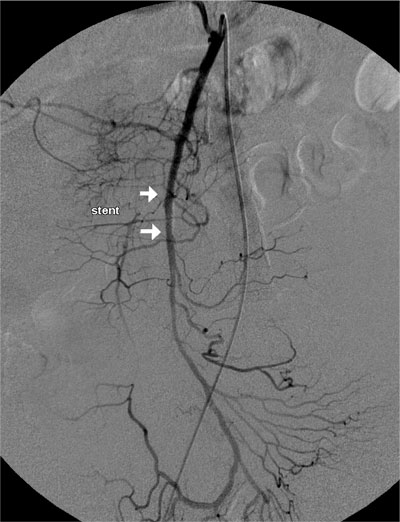

Paciente de 84 anos, sexo feminino, hipertensa, portadora de fibrilação atrial crônica e marcapasso definitivo associado a insuficiência coronariana. Procurou atendimento por apresentar forte dor abdominal em cólica, iniciada há poucas horas e que não cessou com uso de analgésicos tradicionais. Ao exame físico, observou-se ritmo cardíaco irregular por fibrilação atrial crônica e dor abdominal difusa à palpação profunda, sem sinais de descompressão dolorosa do abdome. Indicado estudo angiográfico realizado cerca de 3 horas do inicio da dor, que demonstrou oclusão do terço médio da artéria mesentérica superior. Realizado tratamento endovascular, mediante trombólise mecânica associada ao implante de stent em estenose localizada no terço médio da artéria mesentérica superior, sem intercorrências. Paciente permaneceu internada em Unidade de Terapia Intensiva, encontrando-se hemodinamicamente estável no primeiro dia após o procedimento. Entretanto, como os padrões laboratoriais de acidose metabólica e leucocitose com desvio à esquerda permanecessem, foi submetida à laparotomia exploradora sendo encontrado segmento cianótico, sendo optado preventivamente por ressecção de 70 cm de intestino delgado à 2m do ângulo de Treitz sem intercorrências. Após melhora dos padrões clínicos e laboratoriais, recebeu alta da UTI, permanecendo internada no mesmo Hospital. No 10 dia pós operatório a paciente apresentava desconforto abdominal, sendo realizado nova arteriografia que mostrava a perviedade da artéria mesentérica superior. No trigésimo dia pós operatório a paciente se alimentava e apresentava evacuações normalmente mas mantinha desconforto abdominal e leucocitose. Foi submetida a uma nova laparotomia sem achados de isquemia ou de infecção na cavidade.